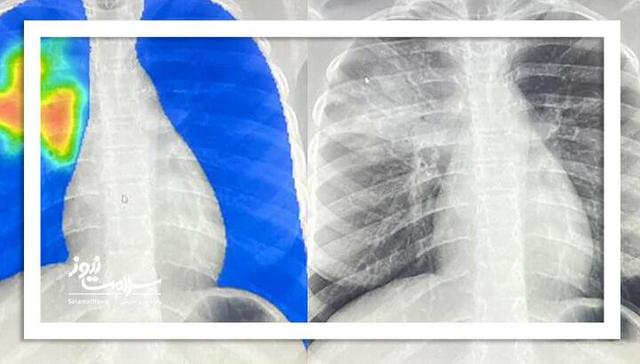

فروش آنتی‌بیوتیک بدون نسخه؛ خطر فاجعه‌ای به نام مقاومت میکروبی

به گزارش پایگاه خبری سلامت نیوز، فروش آنتی‌بیوتیک بدون نسخه؛ خطر فاجعه‌ای به نام مقاومت میکروبی